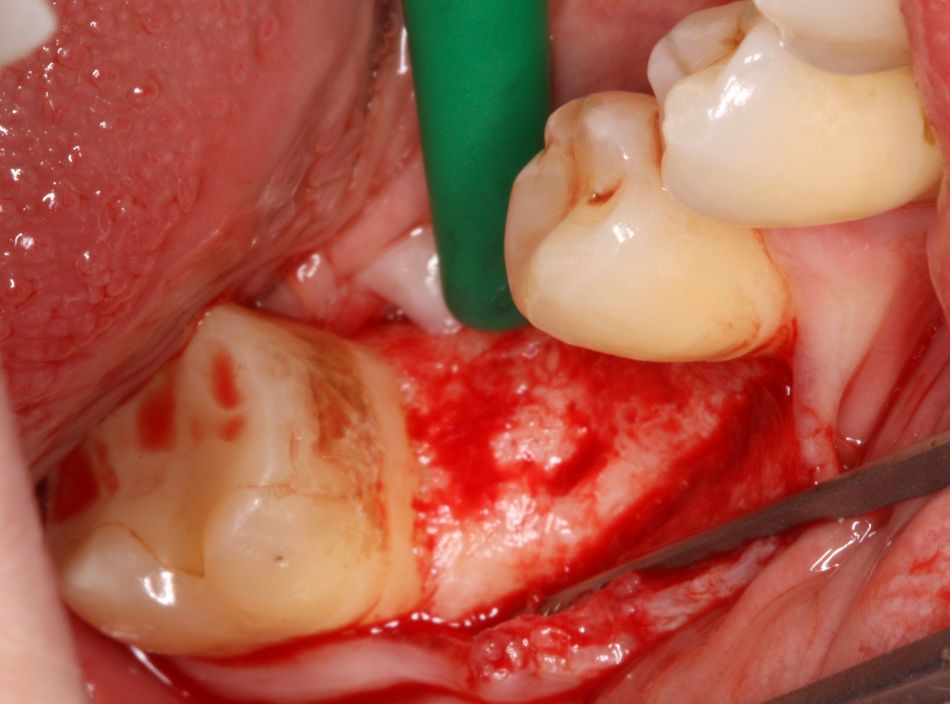

Surgical procedure

After mandibular nerve block, a supracrestal incision was performed from #47 to #45. The mucoperiosteal flap was elevated and the implant bed prepared according to the manufacturer's instructions. Since the bone quality was type 1, a full drill protocol up to 5.2 mm was used. Furthermore, due to the hard bone quality, the insertion of the implant included forward and reverse rotations. The design of the new BLX implant allows the primary stability to be controlled. The primary stability of this implant reached 45 Ncm. No bone augmentation was necessary. The healing abutment was hand-screwed and two stitches were placed in order to close the flap (Figs. 2-15)